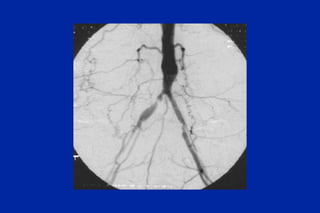

Este documento resume los principales tipos y técnicas de angiografía. Describe brevemente la angiografía, arteriografía, flebografía y linfografía, así como las técnicas de contraste y materiales utilizados. También explica los principales accesos vasculares, la técnica de Seldinger, la angiografía por sustracción digital y algunas técnicas endovasculares comunes.